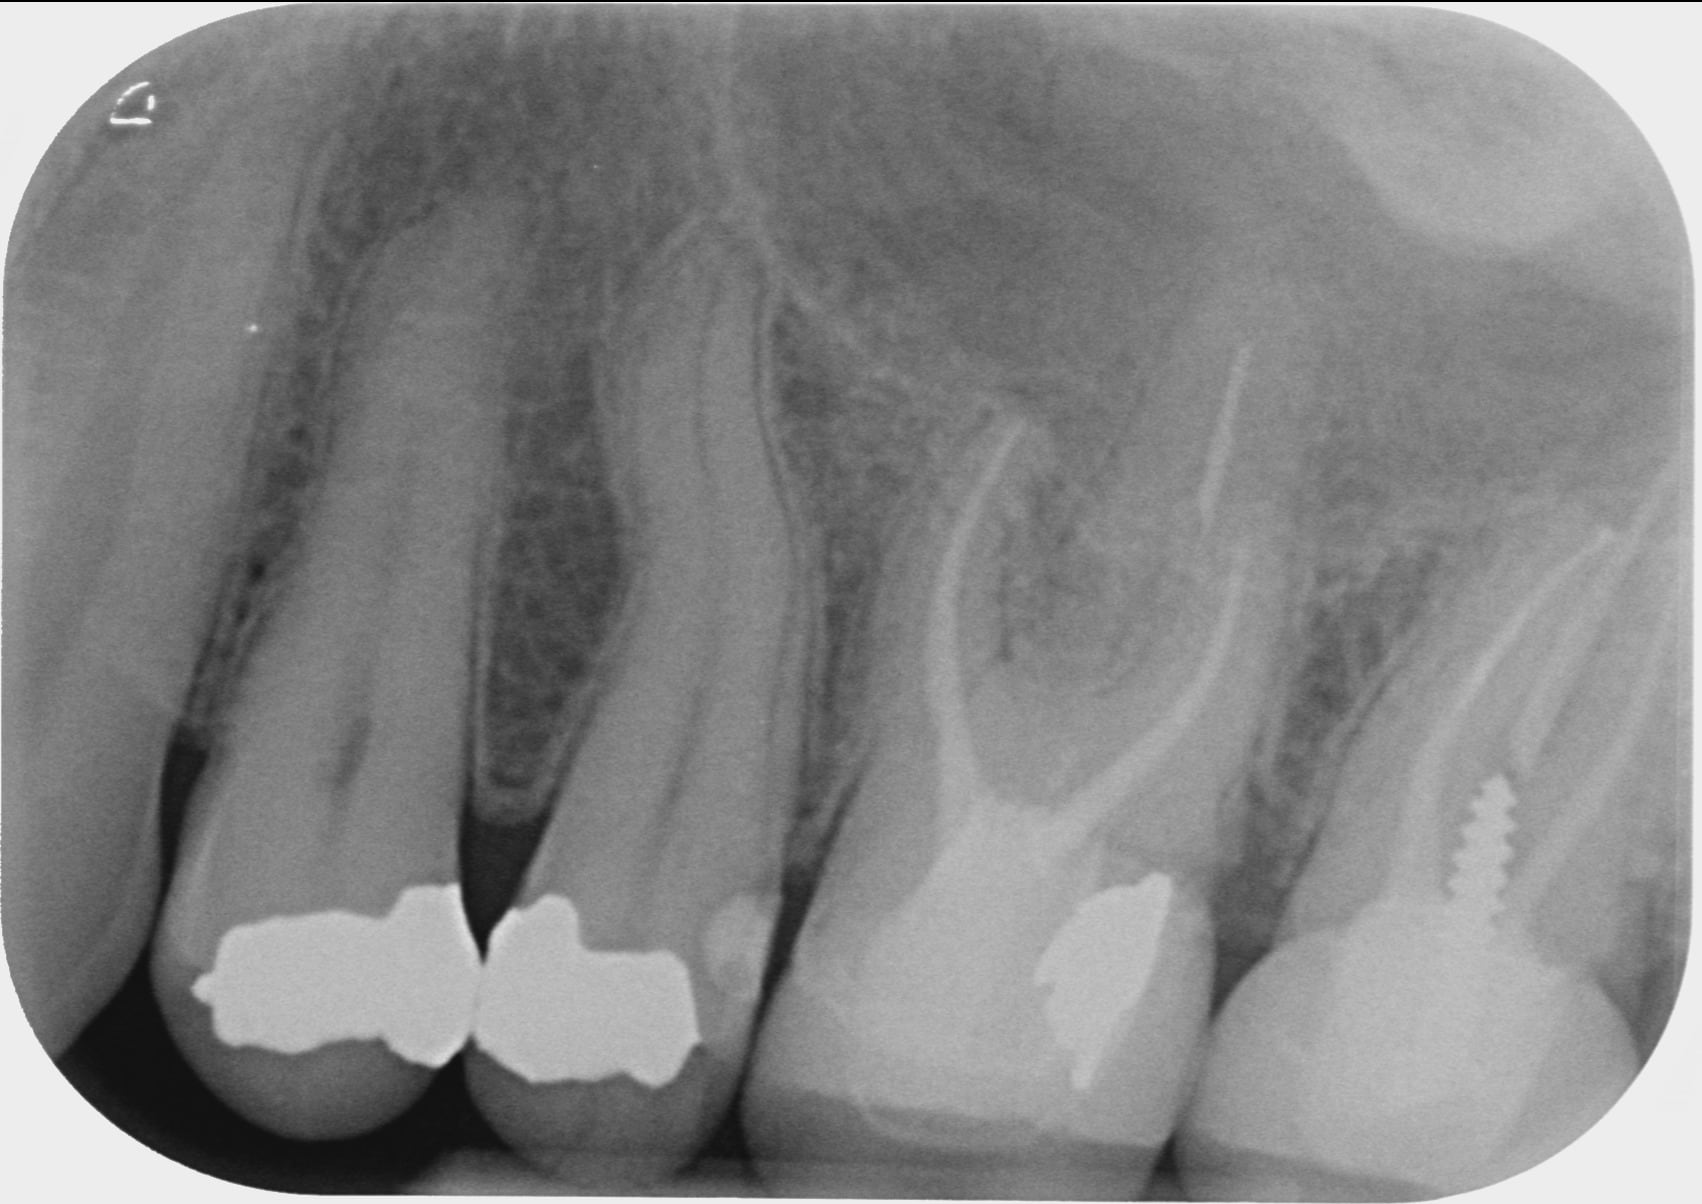

En PJ la rétro de la zone prise en 2016, 2018 et il y a un mois

vraiment je suis paumé : la radio semble nickel : pas de poche, pas de granulome

elle dit : " PJ la rétro de la zone prise en 2016, 2018 et il y a un mois "

tu y vois une perte d os en 3 ans , toi ? moi non .

La couronne de 37 a un profil d'émergence mésial en surcontour

L expression paro existe entre la 6 et la 7 l os cortical disparait au sommet du septum.